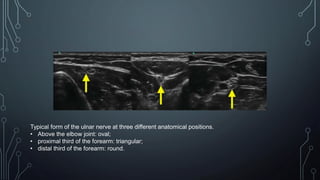

Typical form of the ulnar nerve at three different anatomical positions.

• Above the elbow joint: oval;

• proximal third of the forearm: triangular;

• distal third of the forearm: round.